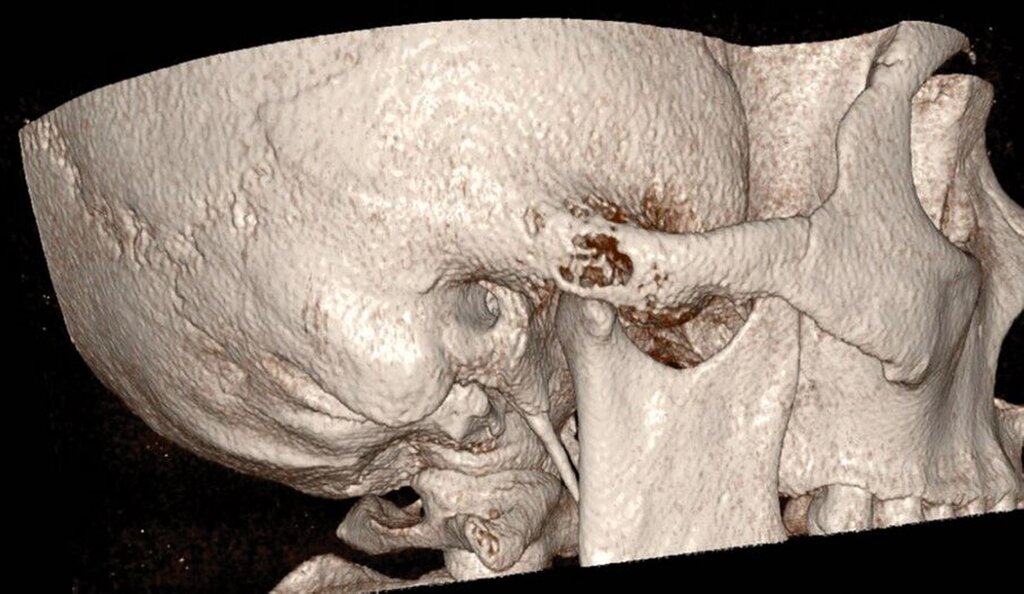

Der operative Eingriff erfolgte in Intubationsnarkose über einen präaurikulären Zugang im kranialen Schläfenbogen (Abbildung 2). Nach stumpfer Präparation und Darstellung der Fossa mandibularis zeigte sich intraoperativ ein kortikal durchbrochenes, strukturell verändertes Knochenareal mit typischer Konsistenz einer fibrösen Dysplasie (Abbildung 3). Es wurde eine gezielte knöcherne Biopsie entnommen (Abbildung 4), wobei keine Infiltration der angrenzenden Weichteilstrukturen oder kritischer anatomischer Nachbarbereiche erkennbar war. Der Eingriff verlief komplikationslos. Die intraoperative Blutung war gering, und der Defekt wurde mit Kollagenschwämmen augmentiert. Der Wundverschluss erfolgte schichtweise. Die postoperative Heilung war regelrecht.